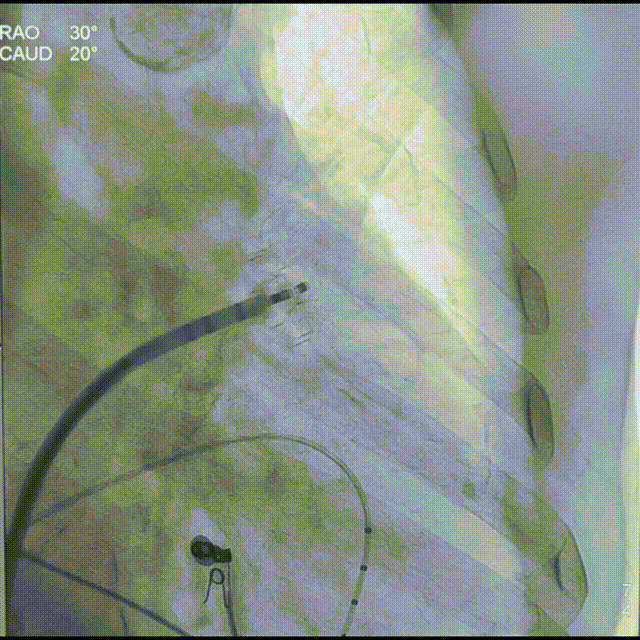

按照Laager®封堵器常规“退-推-退-推”释放方式,依次展开固定盘及封堵盘。造影见固定盘展开在预设位置,封堵LAA内侧;封堵盘上缘位于嵴内,封堵良好无明显残余分流;

Laager®封堵器2429型号固定盘展开后造影